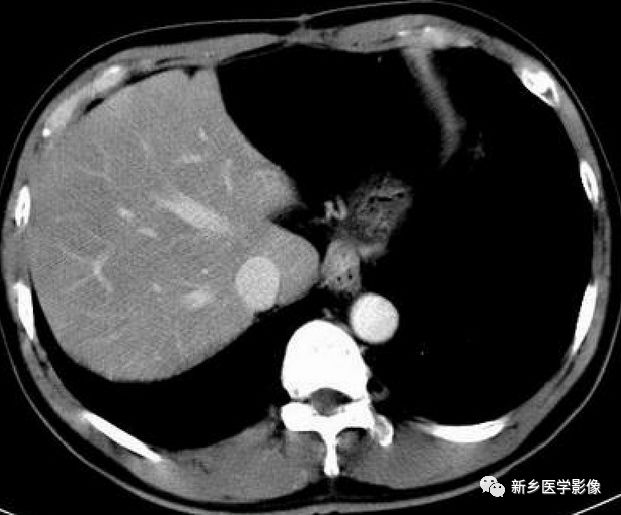

4分叶肝:

肝边缘凹凸不平呈分叶状,如合并肝裂增宽者,可见间位结肠;鉴别诊断:自身免疫性肝炎、肝硬化。